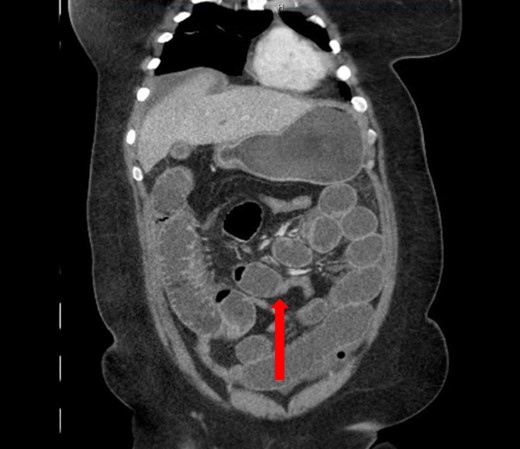

A 40-year-old woman presented to the emergency department with abdominal pain for 4 days. She had previously been seen at an outside hospital 3 days earlier, and was diagnosed with biliary colic. Her pain was constant, and was associated with nausea and vomiting. She had a history of a cesarean section, but no other abdominal surgeries. Her vitals were within normal limits: afebrile at 36.9°C, heart rate 71 beats/minute, blood pressure 143/62 mmHg, respiratory rate 18 breaths/minute, and oxygen saturation 97% on room air. On abdominal exam, she was distended, tender, demonstrated voluntary guarding and was positive for peritonitis. Laboratory values were significant for a white blood cell count of 16.1 K/ul, with 80.2% neutrophils, hemoglobin 14.9 g/dl, hematocrit 45.4%, platelets 349 K/ul and lactic acid 0.9 mEq/L; her chemistry was unremarkable. A computed-tomography (CT) scan of the abdomen and pelvis that was obtained prior to surgical consultation demonstrated the proximal two-thirds of small bowel dilated up to 4 cm, with a sharp transition point in the left mid-abdomen, and collapsed small bowel loops near the cecum. The colon was mostly collapsed. A few distended loops bulged into a paraumbilical hernia, which was 6 cm wide and not the cause of obstruction (Figs 1–3).

Axial view: (A) and (B) arrows pointing to dilated small bowel from the closed loop obstruction. (C) and (D) arrows pointing to the transition point, where the small bowel is collapsed distally.